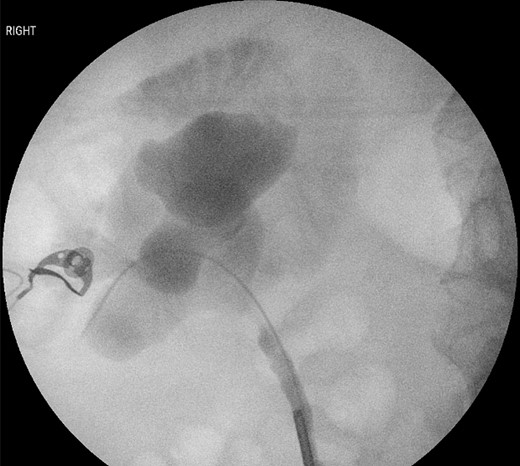

Six-months after her initial presentation, she was diagnosed with recurrent urinary tract infections. Repeat CT to localize the foreign body demonstrated an unchanged position, lodged within the duodenum, extending into the right renal pelvis. A rigid ureteroscopy with a retrograde pyelogram was performed. The foreign body was unable to be visualized, however purulent fluid was egressing from the right ureteric orifice. Contrast was seen filling the renal pelvis and extravasating into the duodenum (Fig. 2). A ureteric stent was inserted for drainage.

Retrograde pyelogram demonstrating contrast extravasating from the right renal pelvis into the duodenum.